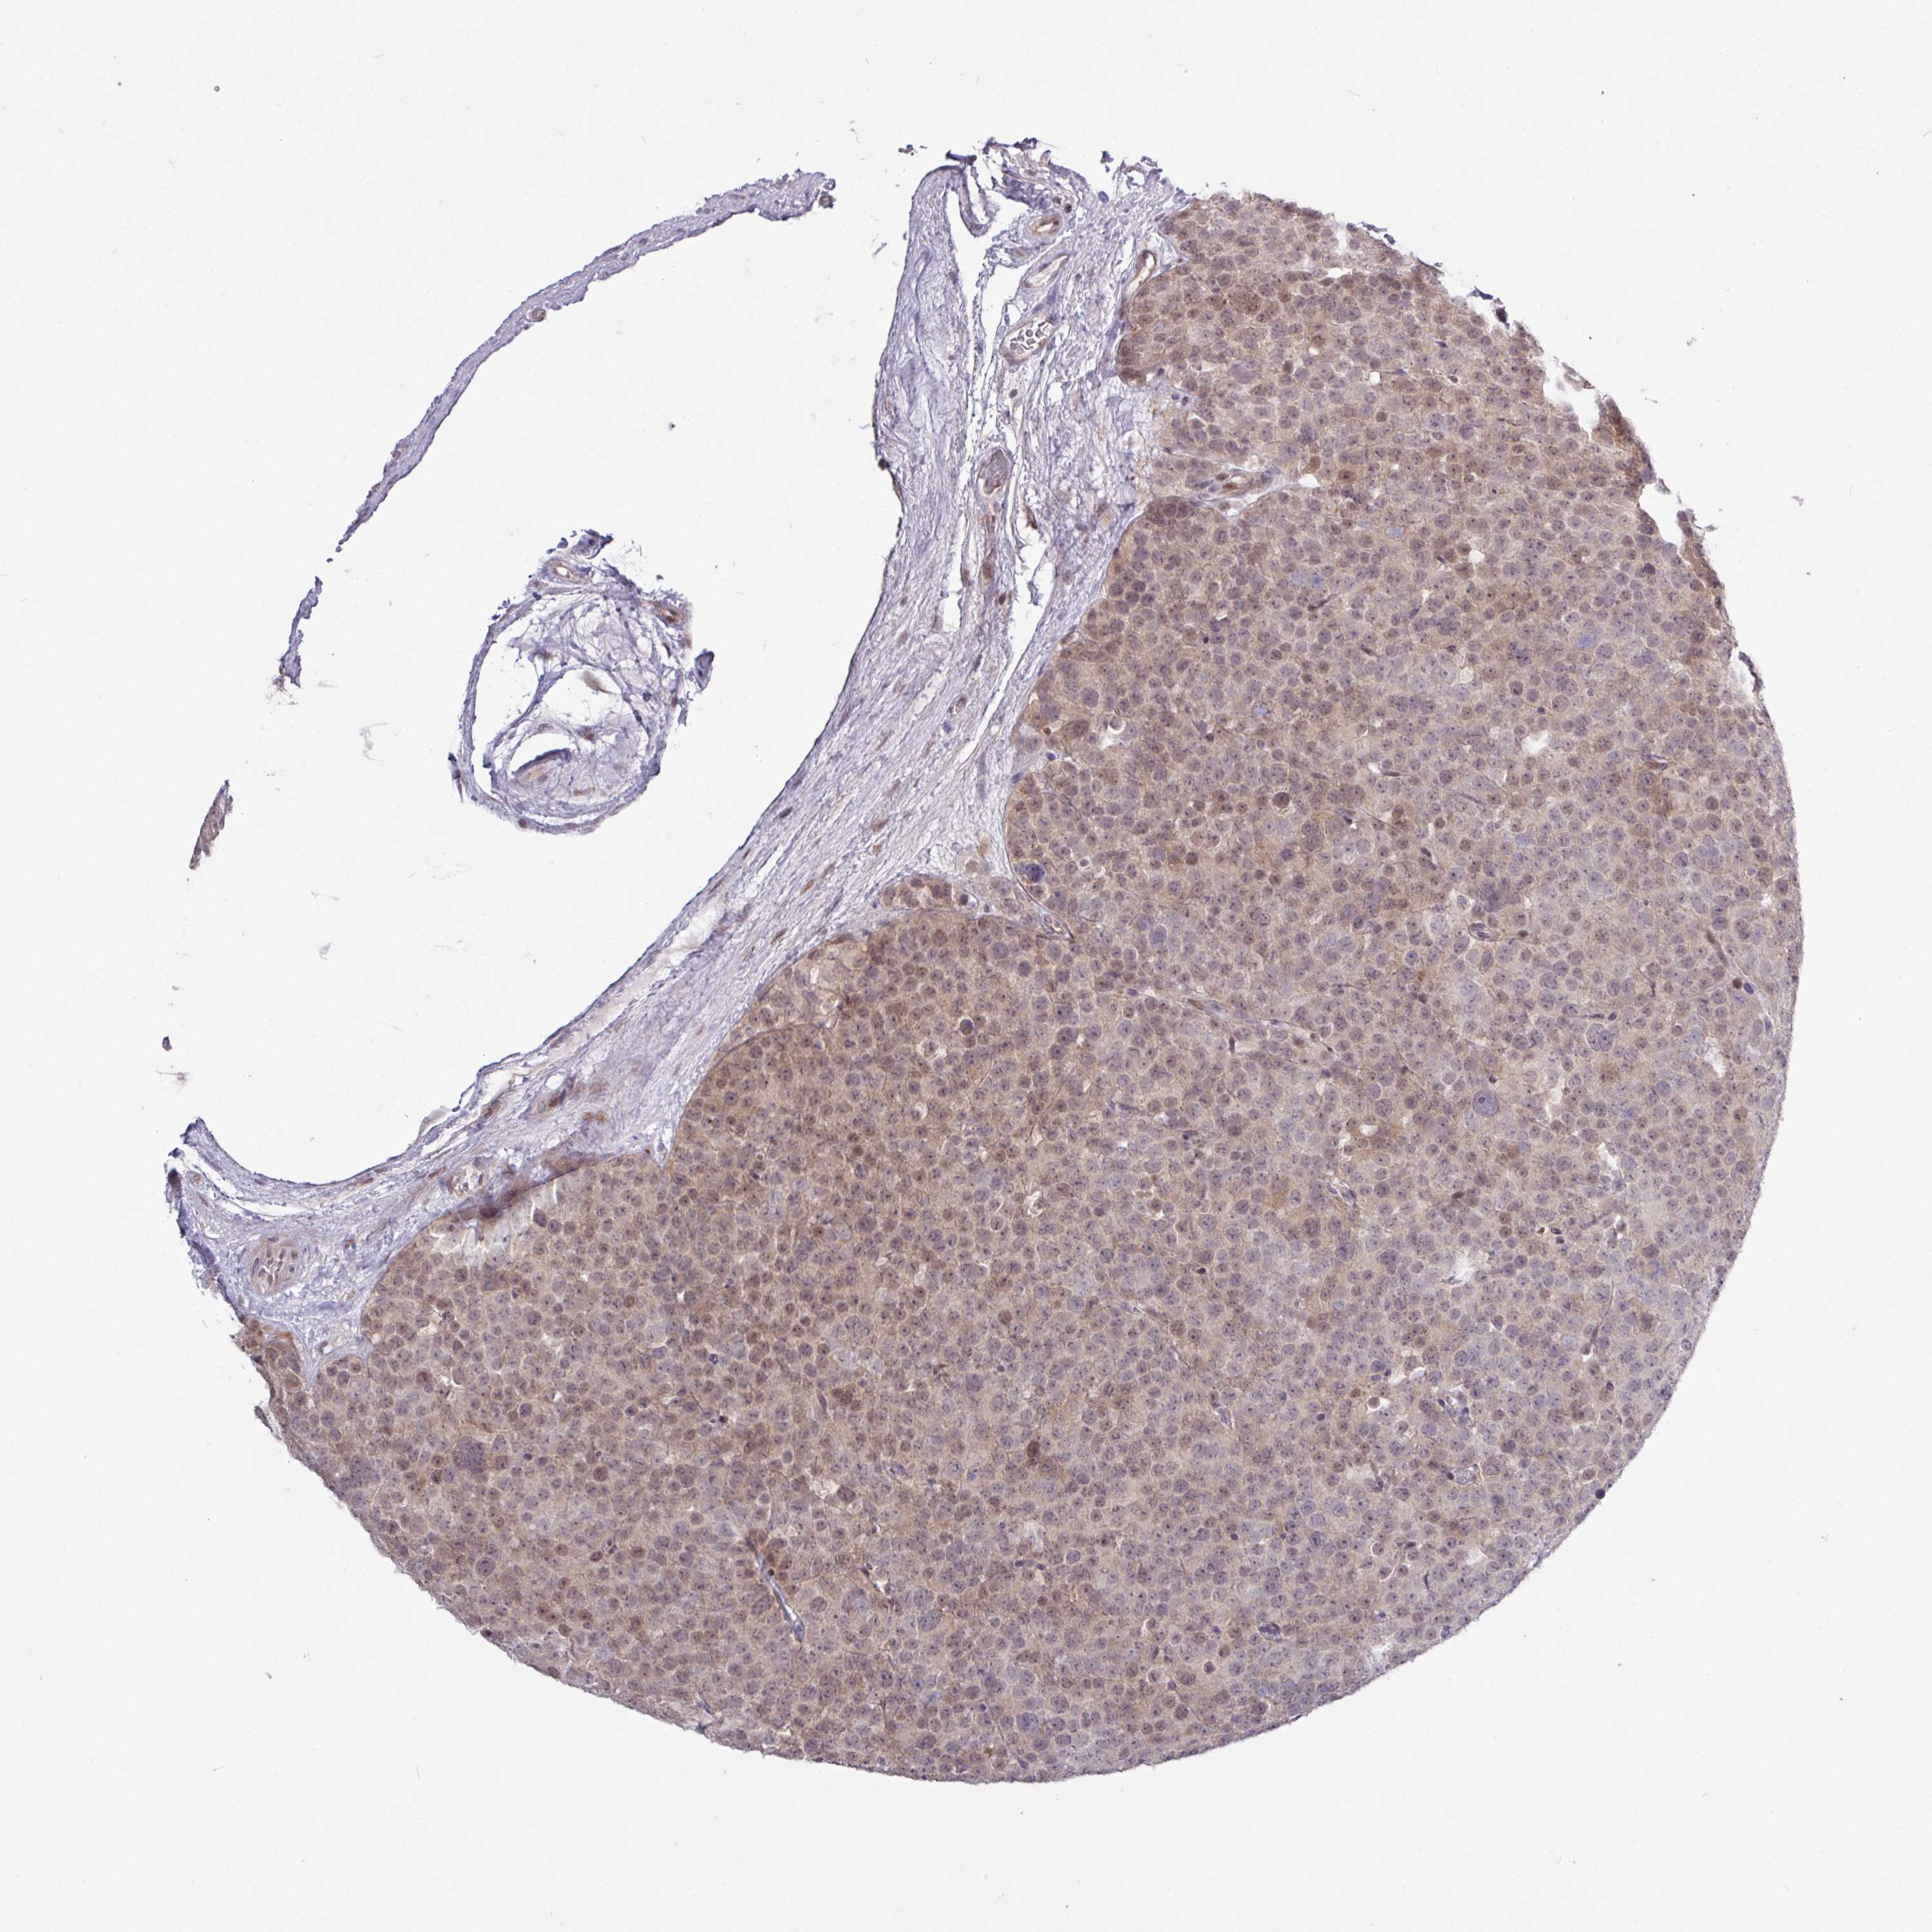

TESTIS CANCER - Protein expressioni

A mouse-over function shows sample information and annotation data. Click on an image to view it in a full screen mode. Samples can be filtered based on level of antibody staining by selecting one or several of the following categories: high, medium, low and not detected. The assay and annotation is described here.

Note that samples used for immunohistochemistry by the Human Protein Atlas do not correspond to samples in the TCGA dataset.

Antibody stainingi

Antibody staining in the annotated cell types in the current human tissue is reported as not detected, low, medium, or high, based on conventional immunohistochemistry profiling in selected tissues. This score is based on the combination of the staining intensity and fraction of stained cells.

Each image is clickable and will lead to virtual microscopy that enables deeper exploration of all samples and also displays staining intensity scores, fraction scores and subcellular localization as well as patient and tissue information for each sample.

Antibody HPA051991

Antibody HPA053174

Staining

High

Medium

Low

Not detected

Intensity

Strong

Moderate

Weak

Negative

Quantity

>75%

75%-25%

<25%

None

Location

Nuclear

Cytoplasmic/membranous

Cytoplasmic/membranous,nuclear

Seminoma, NOS

Carcinoma, Embryonal, NOS